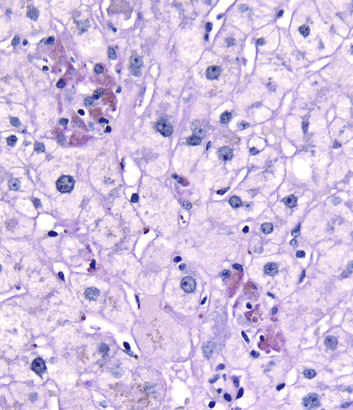

Injured hepatocytes may show several potentially reversible changes, such as accumulation of fat and bilirubin (cholestasis); when injury is not reversible, hepatocytes die by necrosis or apoptosis. Necrosis (Fig. 16.2) is commonly seen following hepatic injury caused by hypoxia and ischemia. Apoptotic cell death (Fig. 16.3) predominates in viral, autoimmune, and drug- and toxin-induced hepatitides.